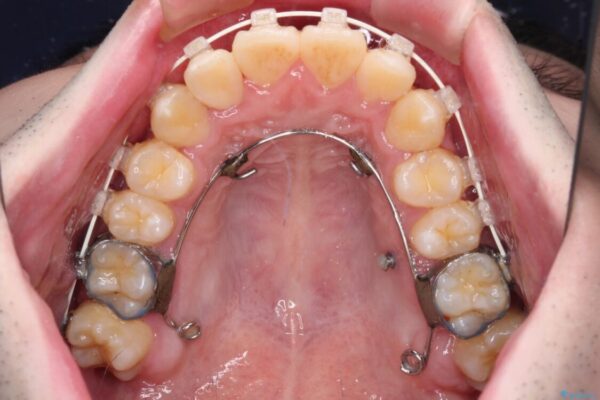

シザーズバイト改善のために補助装置を使用しながら、ワイヤー装置にて全体の歯列を整えることとしました。

シザーズバイトは強く咬合する奥歯を移動させるため、多くの場合においてワイヤー矯正の装置のみでは改善が困難となります。

奥歯の咬み合わせ改善は治療初期からしっかりとアプローチする必要があるため、補助装置を積極的に利用します。

治療途中